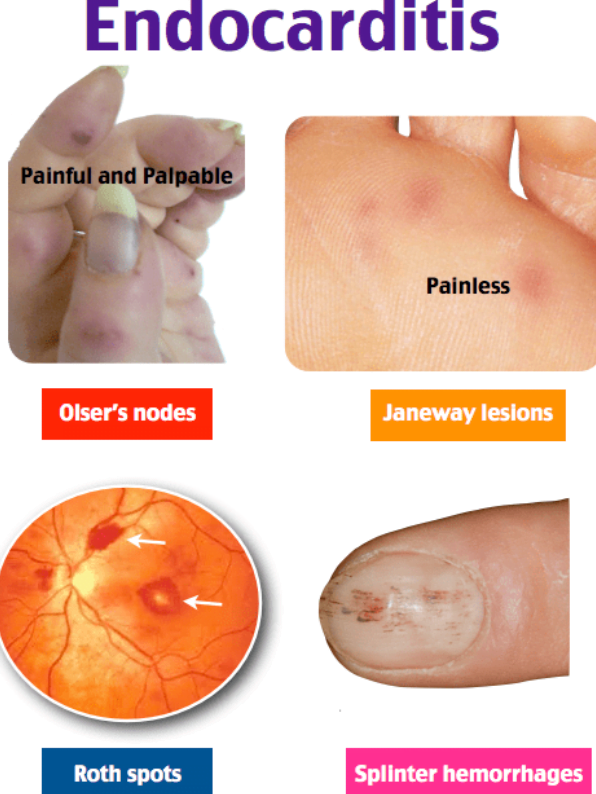

- Endocarditis

- Endocarditis